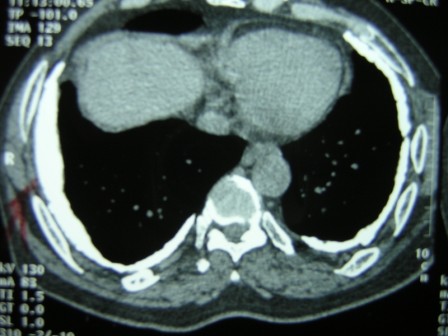

High Resolution CT scan of the lungs (Figure 2) showed bilateral pleural plaques, diffuse pleural thickening and increased interstitial markings. These changes were confirmed on prone films as well. (Figure 3) The calcified pleural plaques are particularly well seen on the mediastinal window of the CT scan (Figure 4).

Figure 3:High Resolution CT scan of the lungs in prone position.

Figure 4: CT scan of the thorax — mediastinal windows.

On the basis of his occupational history and radiological findings, he was diagnosed to have asbestos-induced pleuroparenchymal disease. A two-dimensional echocardiogram showed resting pulmonary arterial pressure of 50 mm Hg with dilated right atrium and right ventricle and normal left ventricular function.